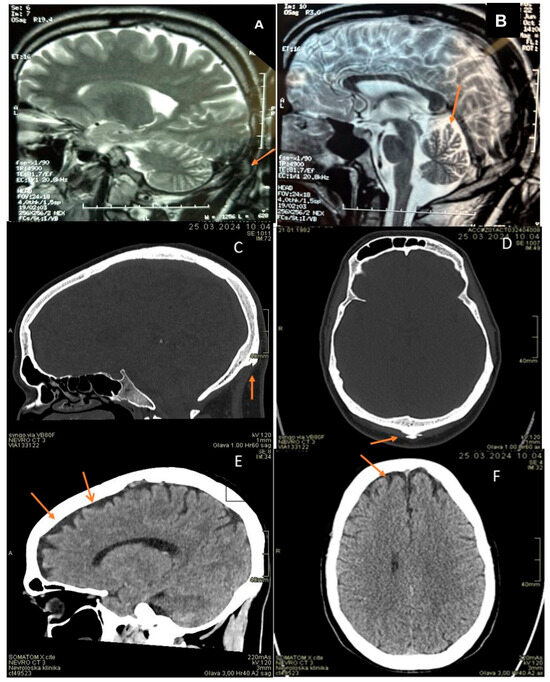

Investigations revealed EMG consistent with axonal motor neuropathy (Table 2). In EEG, posterior background activity was slower due to intermittent theta (6 Hz) frequency. His head MRI showed occipital horn and mild cerebral and more pronounced cerebellar atrophy (Figure 1). Additionally, sinus bradycardia with individual supraventricular extrasystoles was noticed on ECG and spirometry showed moderate obstructive-restrictive ventilatory abnormalities. His serum copper and ceruloplasmin levels were slightly reduced (Table 1).

Figure 1.

(A): patient 1, brain MRI, T2 sagital image: occipital horn (orange arrow). (B): patient 1, brain MRI, T2 sagittal image: dilated frontoparietal and cerebellar sulci (orange arrow). (C,D): patient 2, head CT, bone window, sagital and axial planes: occipital horn (orange arrows). (E,F): patient 2, head CT, soft tissue window, sagittal and axial planes. Mildly dilated frontal sulci (orange arrows).

Nerve conduction studies showed signs of axonal motor neuropathy (Figure 1). EEG was normal. His head CT scan showed occipital horn and mild frontal cerebral atrophy (Figure 1). An electrocardiogram performed after radiofrequency ablation showed sinus rhythm. Spirometry showed mild obstructive ventilatory abnormalities. He had myopia (−6 OD and −6.5 OS). His serum copper and ceruloplasmin levels were slightly reduced (Table 1).